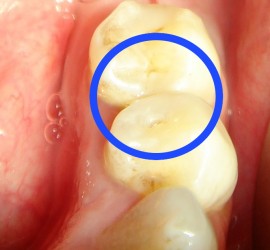

Лечение пульпита. При лечении пульпита перед врачом встают следующие задачи: избавление больного от болевых ощущений, ликвидация инфекционно-токсического очага в пульпе зуба, восстановление формы и функции зуба. Первую помощь больному острым пульпитом может оказать средний медработник или врач любого другого профиля. Она заключается в назначении внутрь обезболивающих препаратов типа анальгина, амидопирина, […]